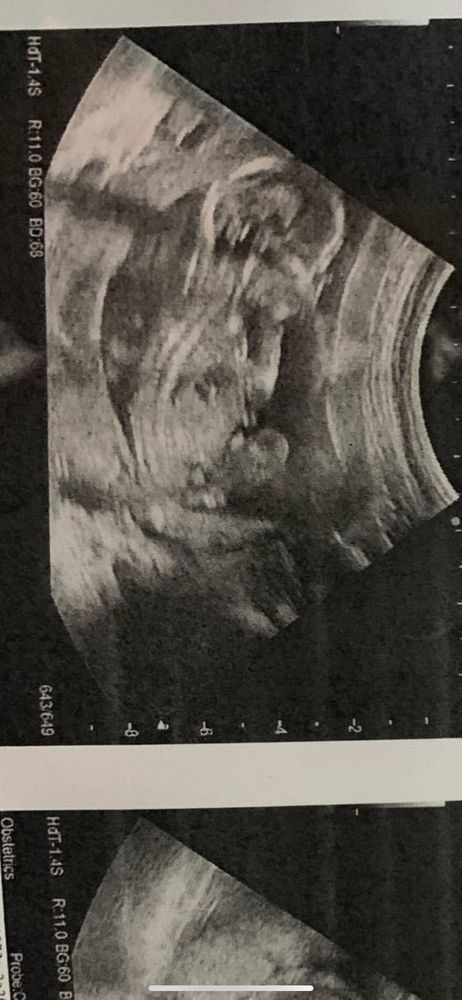

Пол ребёнка/ мальчик или девочка

Пол малышаВсем привет . Подскажите, видно ли тут пол ? Или это ножка так лежит ? Срок 15,4

Даа,мальчик)

Юлия, мне определили , сказали мальчик, но сказали , что оставят на всякий случай 10% что девочка

Xyliganka Tata, просто мы просили написать пол на листик , что дома откроем , фотки где видно пол она удалила и оставила где не видно пол ) но я вот думала это ножка , пока не пригляделась 😅вдруг ошибка

Алина , мне кажется точно мальчик)))

Xyliganka Tata, вида снизу у нас нет ) все фотки такие на узи удалили ))) поэтому не знаю 🤷🏼♀️ Значит будет второй сынок)